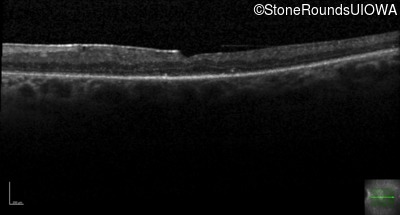

Age at visit: 27 years

Age at visit: 28 years